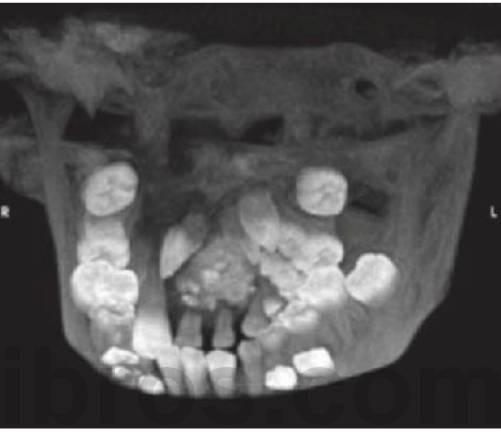

Los dientes supernumerarios surgen como resultado de una geminación de la lámina dental que se produce de forma esporádica o se heredan, como sucede con la displasia cleidocraneal (fig. 9.8).

- Erupción fallida o ectópica de un diente permanente (fig. 9.8B).

- A menudo erupcionan dientes cónicos que se pueden extraer con mucha facilidad (fig. 9.8A).

- Los dientes tuberculados o cónicos invertidos requieren extracción quirúrgica (fig. 9.8D) tan pronto como sea posible para permitir la erupción sin obstáculos del diente permanente.

- Resulta esencial localizar la posición del diente que debe extraerse antes de la cirugía. Pueden realizarse radiografías periapicales que emplean la técnica del desplazamiento del tubo (tube-shift) para localizar el diente, pero siempre entrañan la posibilidad de errores e interpretaciones erróneas. De la misma manera, pueden utilizarse radiografías panorámicas y oclusales maxilares estándar. La proyección oclusal de vértice permite obtener una muestra más precisa de la localización horizontal y anteroposterior, por lo que es la preferida (fig. 9.8C) para ayudar a determinar el procedimiento quirúrgico óptimo. Algunos centros prefieren no utilizar esta vía debido a una excesiva radiación en el cráneo.

- Las técnicas digitales de imagen que utilizan tomografías de haz cónico proporcionan una buena definición e imágenes tridimensionales de la cabeza y el cuello y emiten mucha menos radiación que la tomografía computarizada tradicional (TC) (v. fig. 9.18 más adelante).